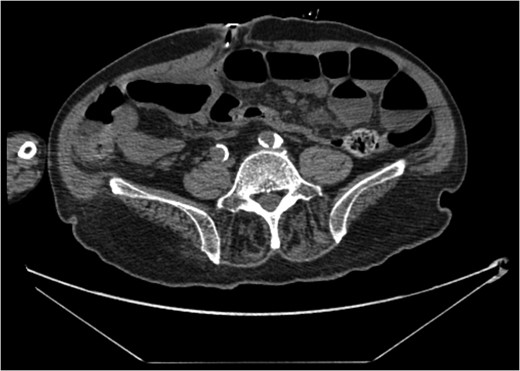

A 68-year-old male nursing home resident presented following dislodgement of a percutaneous endoscopic colostomy (PEC) tube originally sited to prevent recurrent sigmoid volvulus. Computed tomography demonstrated tube migration into the lumen of the recto-sigmoid junction, where it remained for 12 days before passing spontaneously. During this period, the patient remained asymptomatic; the residual colocutaneous fistula functioned as a decompressive valve. Originally, the patient was due to be discharged with early flexible sigmoidoscopy follow-up. However, complex social issues delayed discharge. During his admission, a second PEC tube was successfully inserted next to the previous colostomy site without complication. This is an unusual case and no similar episodes of asymptomatic PEC migration have been reported. We demonstrate that such cases may be offered an appropriate trial of conservative management. Here, we describe our experience and critically appraise the literature.

The patient remained asymptomatic with a soft, non-tender abdomen. The only abnormal clinical finding was the absence of a PEC tube from a patent periumbilical colostomy site.

The patient remained well and the PEC tube passed spontaneously on Day 12, during a bowel motion.